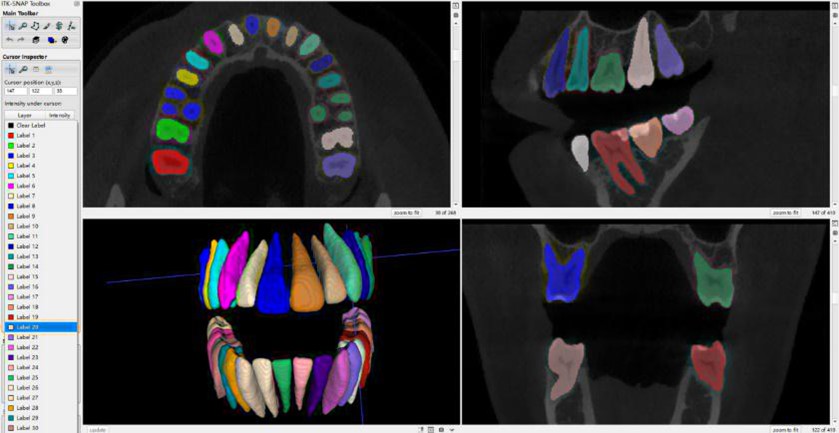

في مجال CBCT تعتبر هذه الدراسة ثورة في مجال الأشعة ثلاثية الأبعاد (CBCT). تم استخدام نموذج SAM المطور من شركة Meta وتكييفه طبياً (MedSAM) لتجزئة الأسنان والقنوات العصبية بشكل تلقائي وفوري. هذه التقنية تغلبت على مشكلة الوقت الطويل الذي كان يستغرقه الأطباء في تحديد موقع العصب السنخي السفلي قبل زراعة الأسنان.[1]

الشكل [1]: [1] CBCT

كما تناولت دراسة حديثة بعنوان “تجزئة الأسنان وتصنيفها في الصور المقطعية المحوسبة (CBCT) باستخدام الشبكات العميقة ثلاثية الأبعاد، مما يساهم في تجاوز مشكلات تداخل الجذور وتسهيل التخطيط للجراحات المعقدة وزراعة الأسنان [22].